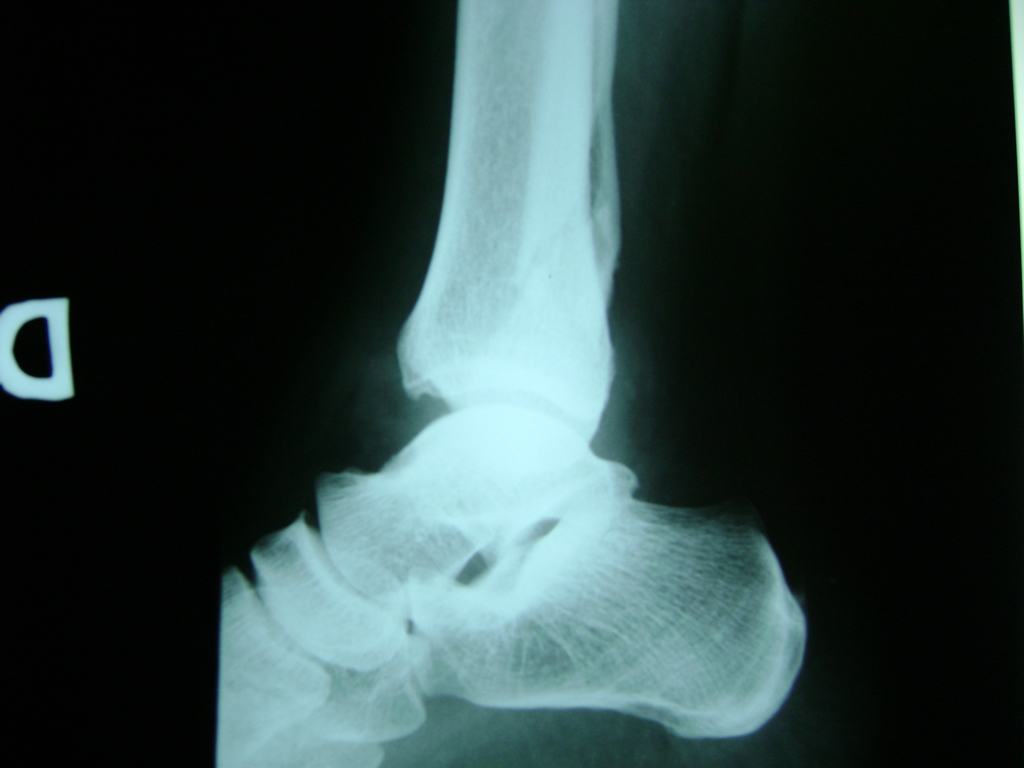

Una fractura de tobillo es la rotura de uno o más de los huesos del tobillo. Estas fracturas pueden ser:

• Parciales (el hueso está sólo parcialmente fisurado, no del todo).

• Completas (el hueso está perforado y está en 2 partes).

• Producirse en uno o ambos lados del tobillo.

Algunas fracturas de tobillo pueden requerir cirugía si:

• Los extremos de los huesos están desalineados entre sí (desplazados).

• La fractura se extiende hasta la articulación del tobillo (fractura intra-articular).

• Los tendones o ligamentos (tejidos que sujetan los músculos y los huesos entre sí) están rotos.

• El médico cree que sus huesos probablemente no sanen apropiadamente sin cirugía.

• El médico considera que la cirugía puede permitirle una recuperación más rápida y confiable.

• En los niños, la fractura involucra la parte del hueso del tobillo donde el hueso está creciendo.